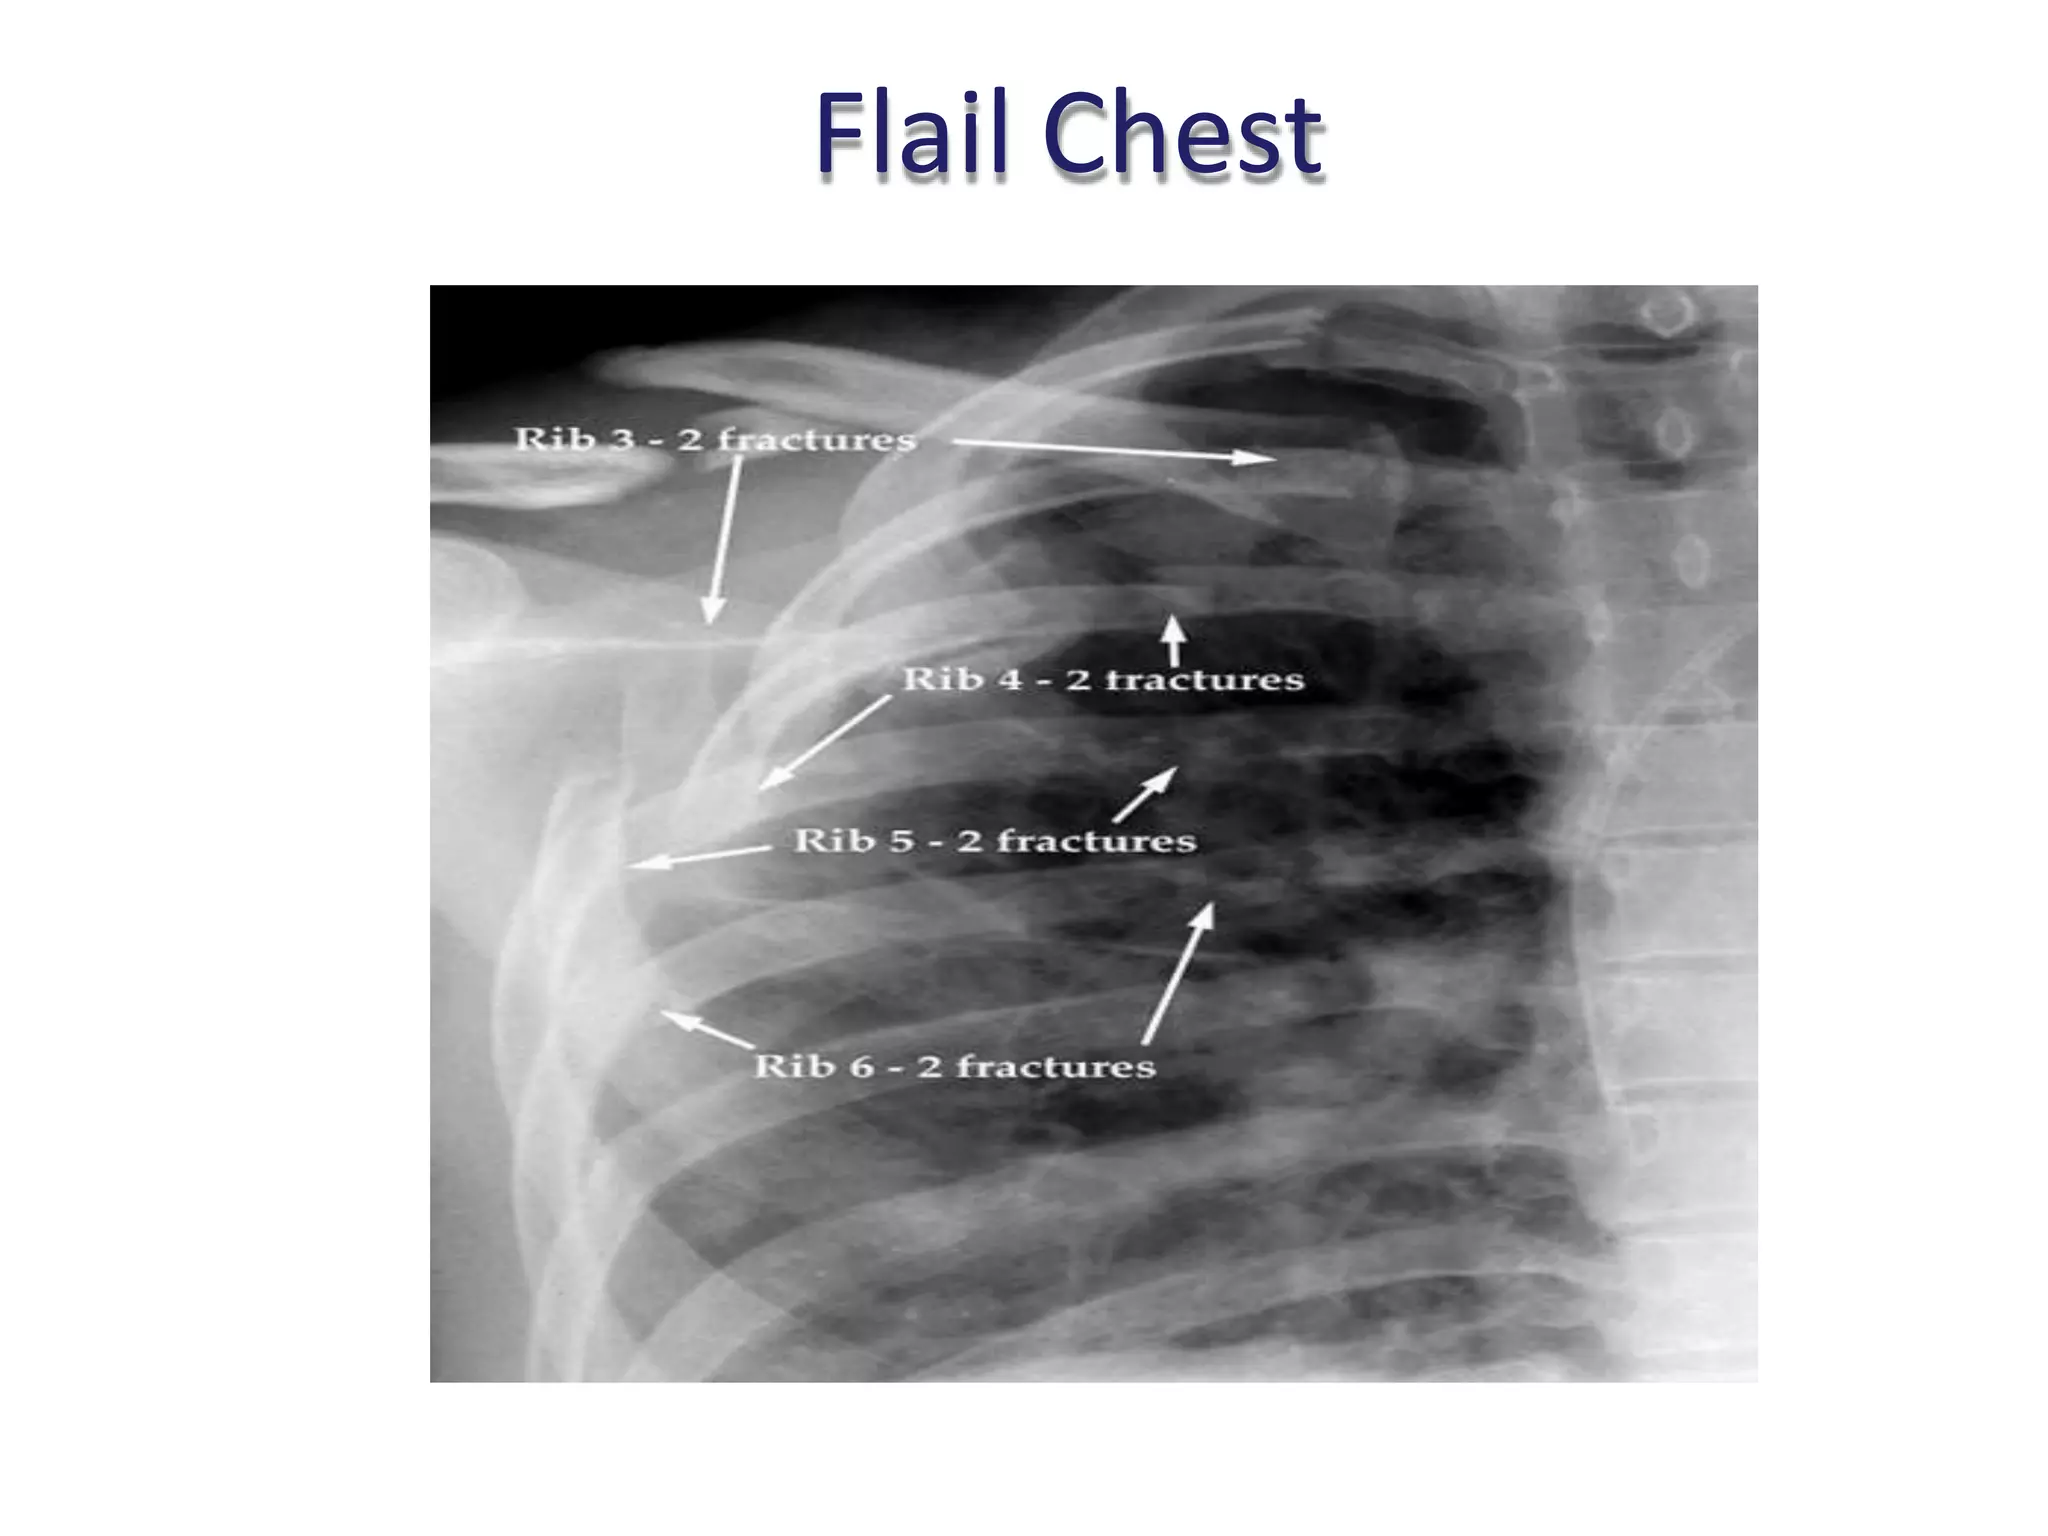

What Is The Best Definition Of Flail Chest . Flail chest is defined as three or more adjacent ribs that are fractured in at least two places. Flail chest is a traumatic condition of the thorax. It may occur when 3 or more. Flail chest is an injury that occurs typically following a blunt trauma to the chest. The most common causes of flail chest are direct blows to the chest, car accidents, and falls. Less commonly, flail chest can occur when two ribs on both sides of the chest are. Flail chest is typically a result of major blunt trauma to the chest wall. Flail chest — defined as two or more contiguous rib fractures with two or more breaks per rib — is one of the most serious of these injuries and is. Flail chest is a particular kind of rib fracture that is defined as three (or more) ribs that are broken in two (or more) places. When three or more ribs.